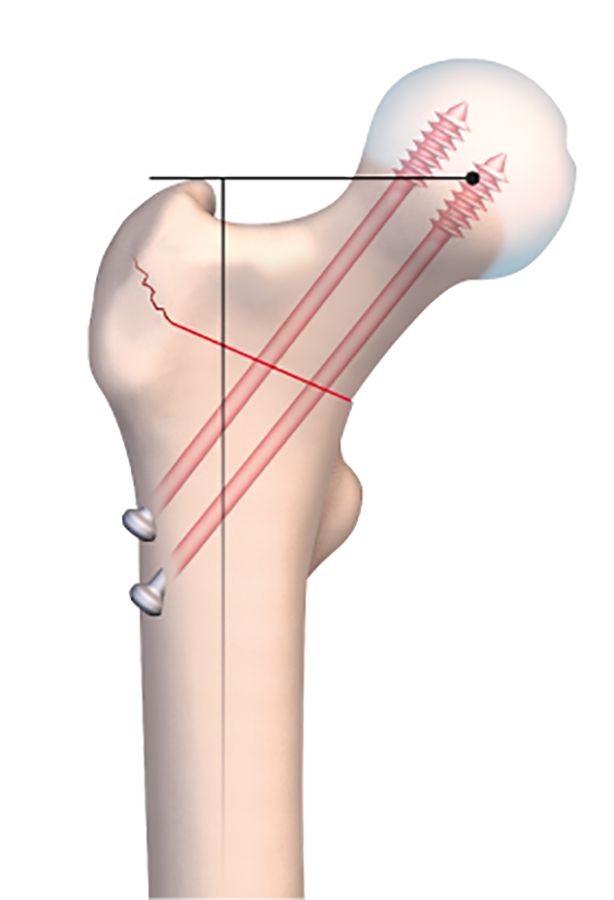

The osteotomy line is usually situated at the base of the neck. It should be as horizontal as possible to improve postoperative stability and avoid any slipping or instability (Fig. 2a).

For a varus-producing osteotomy, a wedge can be removed from the medial base, matching the desired angle of correction. The higher the line, the more accurate the wedge calculations must be because it is all to easy to exaggerate the valgus correction by having the line too close to the neck. The preoperative planning must be just as meticulous as for the traditional technique. We use new computer tools to simplify and even simulate this type of surgery.

This osteotomy is easy to repair, using the same technique as for a normal badly impacted fracture of the base of the neck of femur, with two or three large diameter cannulated screws.

This makes it much easier to guide a pin into the osteotomy line that has just been created. The pin should of course sit just within the osteotomy line, without going any further. Applying compression will close the line and fix the pin in the neck and head of femur. With the osteotomy line closed and the pin in place, the final stage is to insert a 7mm cannulated screw to stabilize the fixation. A second or even third screw may be used if necessary. The image intensifier should be used to check the correct placement of the screws (Fig. 2e).